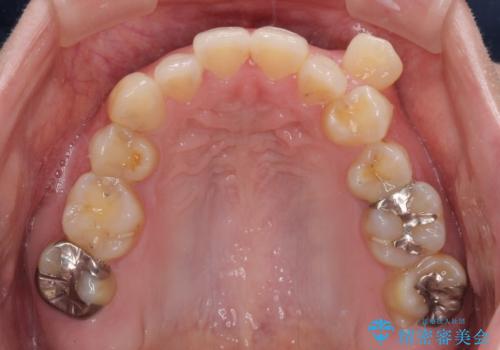

- 左上の八重歯と前歯のデコボコを気にして来院された患者様です。

下顎が左側にズレており、下顎前歯は1歯欠損していたため、左上小臼歯1本を抜歯し、ワイヤー装置にて矯正治療を行うこととしました。

骨格のズレと歯の欠損があったため、仕上がりの調整に時間がかかると思いましたが、舌突出癖の改善や顎間ゴムの装着をしっかりと行ってくださったので、速やかに治療を終えることができました。